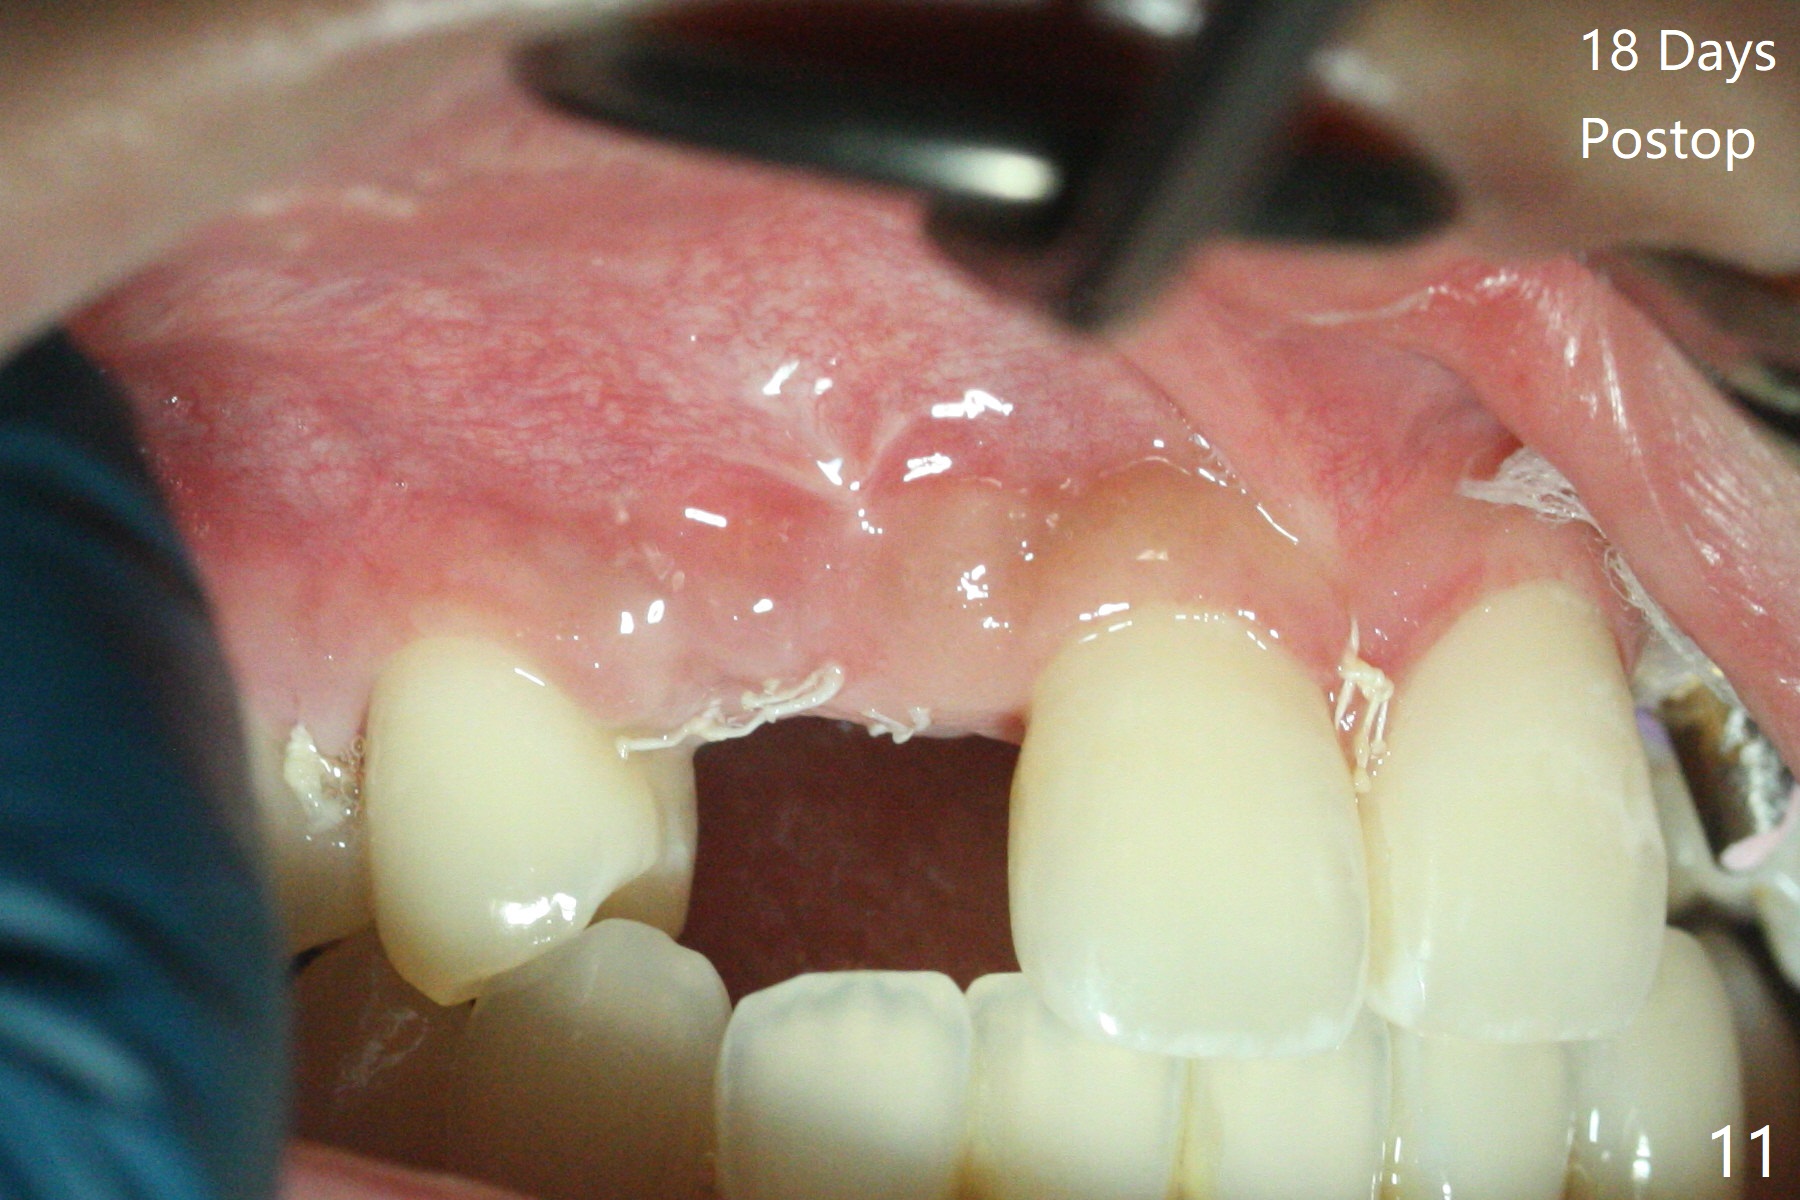

18岁男从外州大学回来,无症状,但是6号牙(右上尖牙)颊侧瘘道(图一,二(角化龈充分(箭头))),根尖片显示植体近中骨吸收(图三:*),而对侧植体仿佛骨整合(图四)。患侧切开后发现植体颊侧暴露,松动。拔除后骨缺损由粘性骨粉修复(图七,九:*),覆盖PRF膜(图七:P)和带钛网(图九:^)不可吸收膜(图五-七),后者用两个小钉子固定(图六(腭侧),七(颊侧),九),使用新的刀片和一个特殊尖头剥离器在颊侧骨膜下相当广泛分离,使用PTFE缝线,粘膜下水平褥式缝合之后(图八:箭头),多个垂直间断缝合,两个乳头垂直褥式缝合。术后一周伤口没有裂开,术后疼痛肿胀已经消退(图十)。术后十八天牙槽嵴仿佛比对侧还要宽(图十一,三与图十二,四(取模)对比)。术后5.5个月伤口没有裂开,牙槽骨,角化龈宽(图十六),与钛网和两个小钉子固定有关(图十五,十七)。CT显示牙槽骨只能容纳2.5或者3.0毫米植体(图十八)。11号牙植体牙冠粘固后没有骨质吸收(图十九),其实10,11号牙颊侧骨板隆起(图二十至二十二),而6植体失败,颊侧骨板吸收,甚至累及5号牙(图十七)。